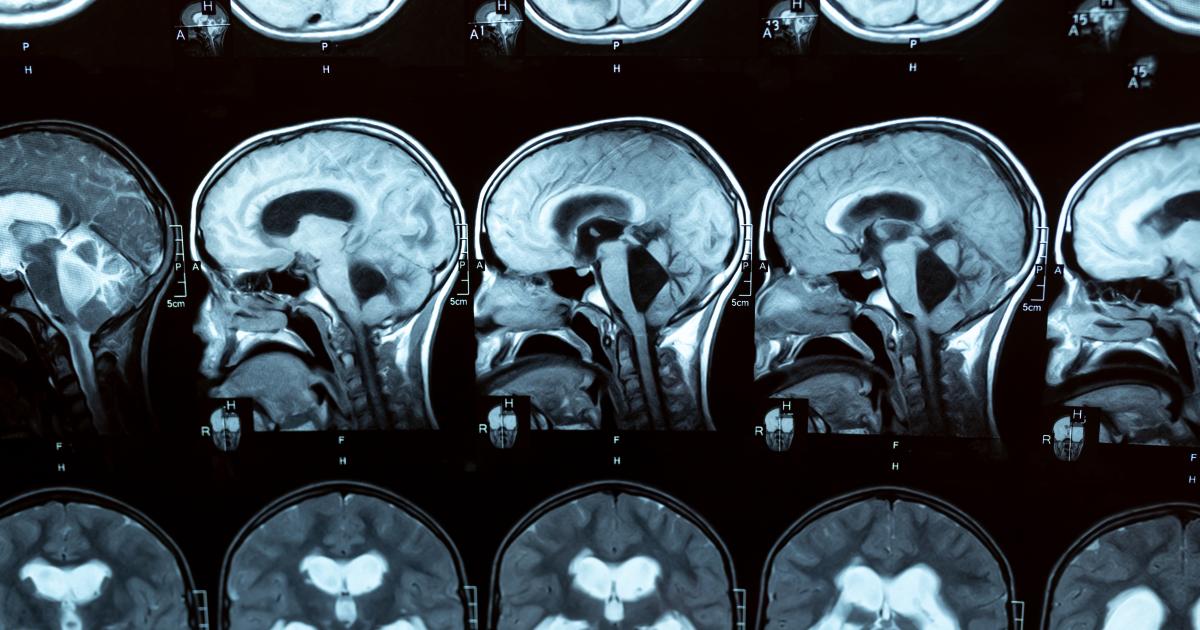

L'hydrocéphalie est une accumulation de liquide dans les cavités du cerveau (appelées ventricules), ce qui provoque leur élargissement et augmente éventuellement la pression sur le cerveau. L'hydrocéphalie est loin d'être rare dans le monde. Aux États-Unis, environ 1 bébé sur 500 naît avec une hydrocéphalie, et un plus grand nombre d'entre eux développent la maladie au cours des deux premières années de leur vie. L'hydrocéphalie n'est pas non plus l'apanage des enfants : chez les adultes, elle peut survenir à tout moment, en particulier après une infection ou une hémorragie intracrânienne, ou après l'âge de 60 ans, avec une prévalence qui augmente avec l'âge. En fait, elle est souvent sous-diagnostiquée dans cette tranche d'âge car les symptômes peuvent être attribués à la maladie d'Alzheimer ou à la maladie de Parkinson. Cela signifie évidemment que de nombreuses personnes - jusqu'à 10 % des patients atteints de démence - pourraient vivre avec une maladie traitable et non dégénérative. Imaginez ce que cela pourrait signifier en termes de qualité de vie, non seulement pour les malades, mais aussi pour leurs proches et les personnes qui s'occupent d'eux.